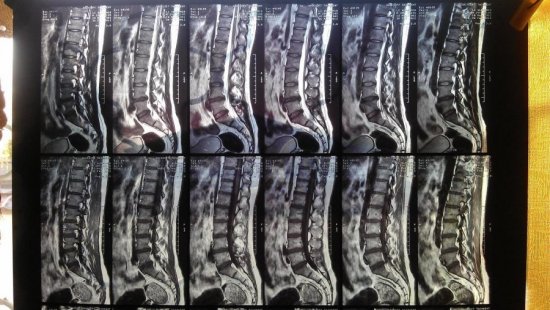

Рентген позвоночника

Часто патологические изменения крестцового и копчикового сегмента при рентгенологическом исследовании не проявляются